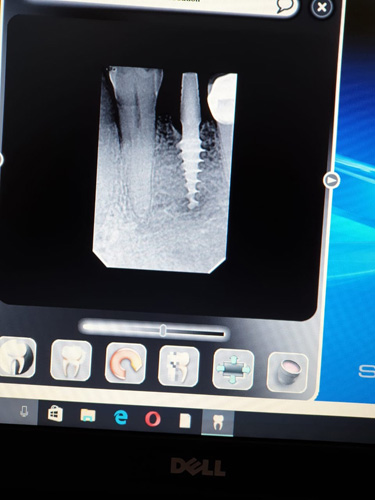

X-ray Imaging of Patients undergoing Treatment